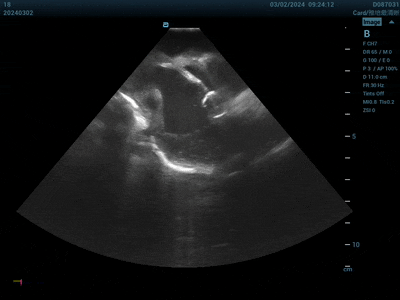

視頻顯示動物實(shí)驗(yàn)中,在ICE引導(dǎo)下,PFApple緊貼心內(nèi)膜進(jìn)行消融